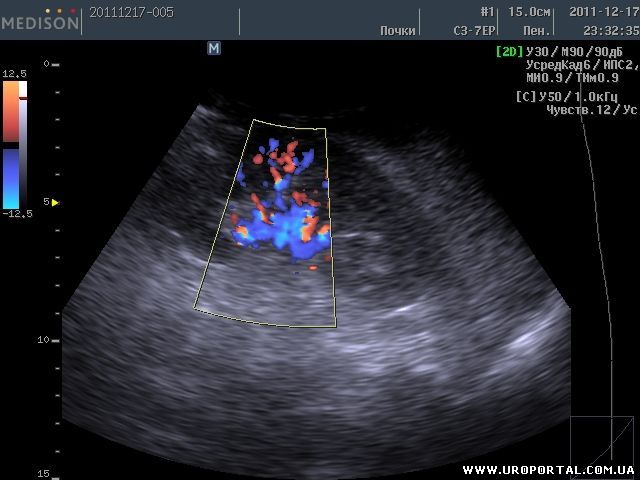

ЦДК сосудов почек: что это и как проводится

Раздел: Фотоэссе